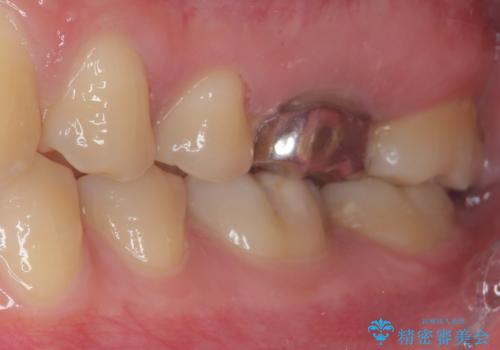

右下の銀の詰め物は、外してむし歯を除去した後、セラミックインレーにて修復することとしました。

左上の銀歯は、銀歯の下に金属の土台が入っているため、その土台を除去し、ファイバーコアにやり替えて、オールセラミッククラウンにて補綴することとしました。